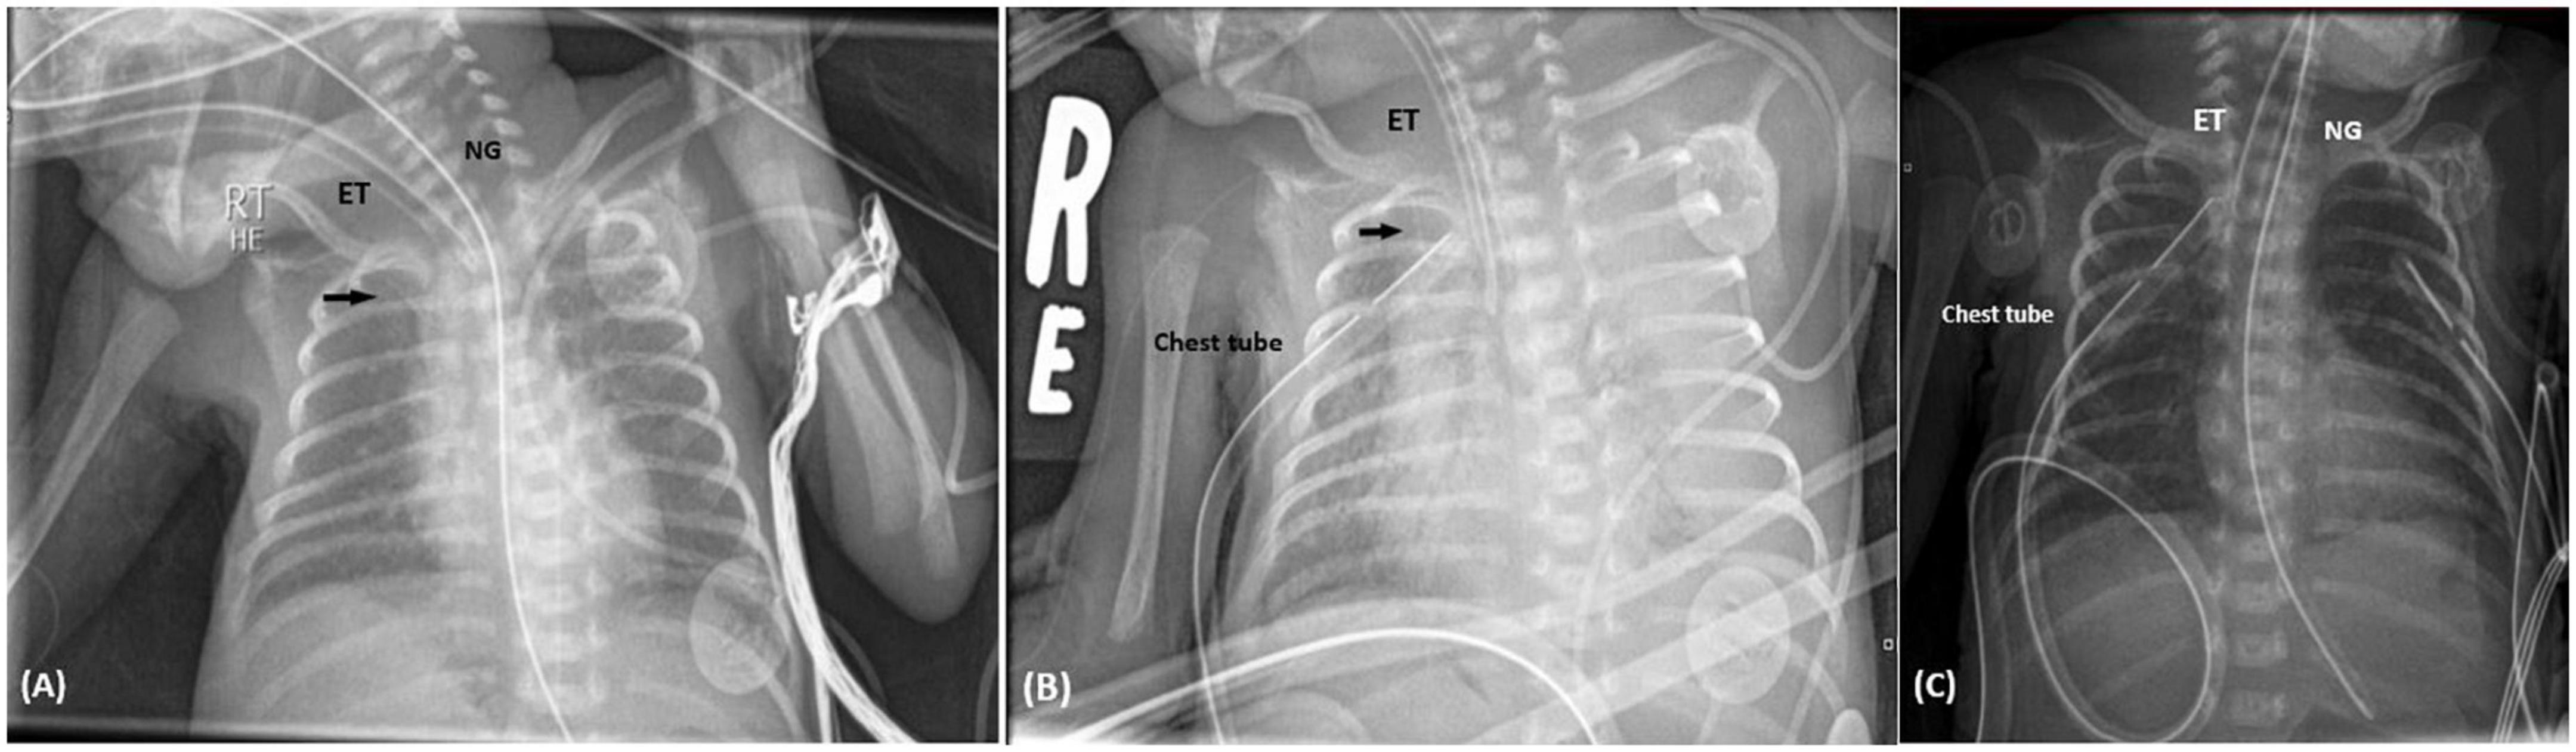

A 667-gram newborn female, product of 24-week triplets’ gestation, was delivered via cesarean section due to preterm premature rupture of membranes, to a 32-year-old mother. APGAR scores were 7 and 8 at 1 and 5 min, respectively. The newborn was admitted to NICU for the management of extreme prematurity, extreme low birth weight, and respiratory distress. She required intubation and surfactant administration. On the first day of life, umbilical venous and umbilical arterial catheters were placed for blood withdrawal, and for administration of fluids, antibiotics, and nutrition. On the third day of life, PICC was inserted through the right basilic vein for administration of total parenteral nutrition. Chest imaging was performed after insertion and showed the line through the left brachiocephalic vein, with the tip reaching the subclavian vein region. Accordingly, the PICC was retracted 2.5 cm (Figure 1A). Her stay was complicated by right sided pneumothorax on the 11th day of life that required chest tube insertion. On her 16th day of life, she developed sudden decrease in blood pressure reaching a systolic pressure of 35 mmHg, associated with frequent episodes of decreased oxygen saturation down to 60%. As a result, the ventilator settings were adjusted, the peak inspiratory pressure/positive-end expiratory pressure (PIP/PEEP) were increased from 17/3 to 21/5 cm H2O, FiO2 was increased, and she was given a bolus of normal saline. Arterial blood gases at that time were significant for acidosis, with a pH of 7.13, pCo2 of 70 mmHg, and base deficit of −7. Urgent imaging of chest was obtained and revealed moderate left-sided pleural effusions with collapse of the left lung (Figure 1B). Point of care ultrasound was performed and confirmed the presence of moderate to large left-sided pleural effusions reaching the apex with underlying collapse of the lung. Interestingly, the pleural effusions appeared slightly complex containing internal debris on ultrasound. Subsequently, left chest tube was inserted, which drained 27 ml of milky white fluid. Thereafter, the PICC line was removed and another one was inserted through the right femoral vein. Biochemical analysis of the fluid was remarkable for elevated triglycerides of 2,427 mg/dL, elevated glucose of 509 mg/dL, proteins of less than 2 g/dL, and albumin of less than 2 g/dL. Blood tests showed plasma triglycerides of 82 mg/dL, protein 45 g/dL, and albumin 33 g/dL. The results were consistent with pleural effusion secondary to TPN extravasation. Chest imaging performed 2 days later showed resolution of the pleural effusions (Figure 1C). In addition, the patient had marked improvement in clinical status.

FIGURE 1

Figure 1. (A) Supine chest radiograph following PICC insertion in Case I. Chest X-ray performed in supine position, revealed the PICC inserted through the right basilic vein reaching the left subclavian vein. According to this image, the PICC was retracted 2.5 cm. The black arrow identifies the PICC. NG, nasogastric tube; ET, endotracheal tube. (B) Supine chest radiograph following the sudden deterioration in clinical status. Chest X-ray was carried out when the patient had sudden cardiopulmonary decompression. It revealed total whitening of the left lung, as shown on the left side of the image, representing total collapse with left sided pleural effusion. The PICC is represented by the black arrow. ET, endotracheal tube. (C) Chest imaging 2 days following chest tube insertion. Chest X-ray showed complete resolution of the pleural effusion, and normal aeration of the left lung. NG, nasogastric tube; ET, endotracheal tube.